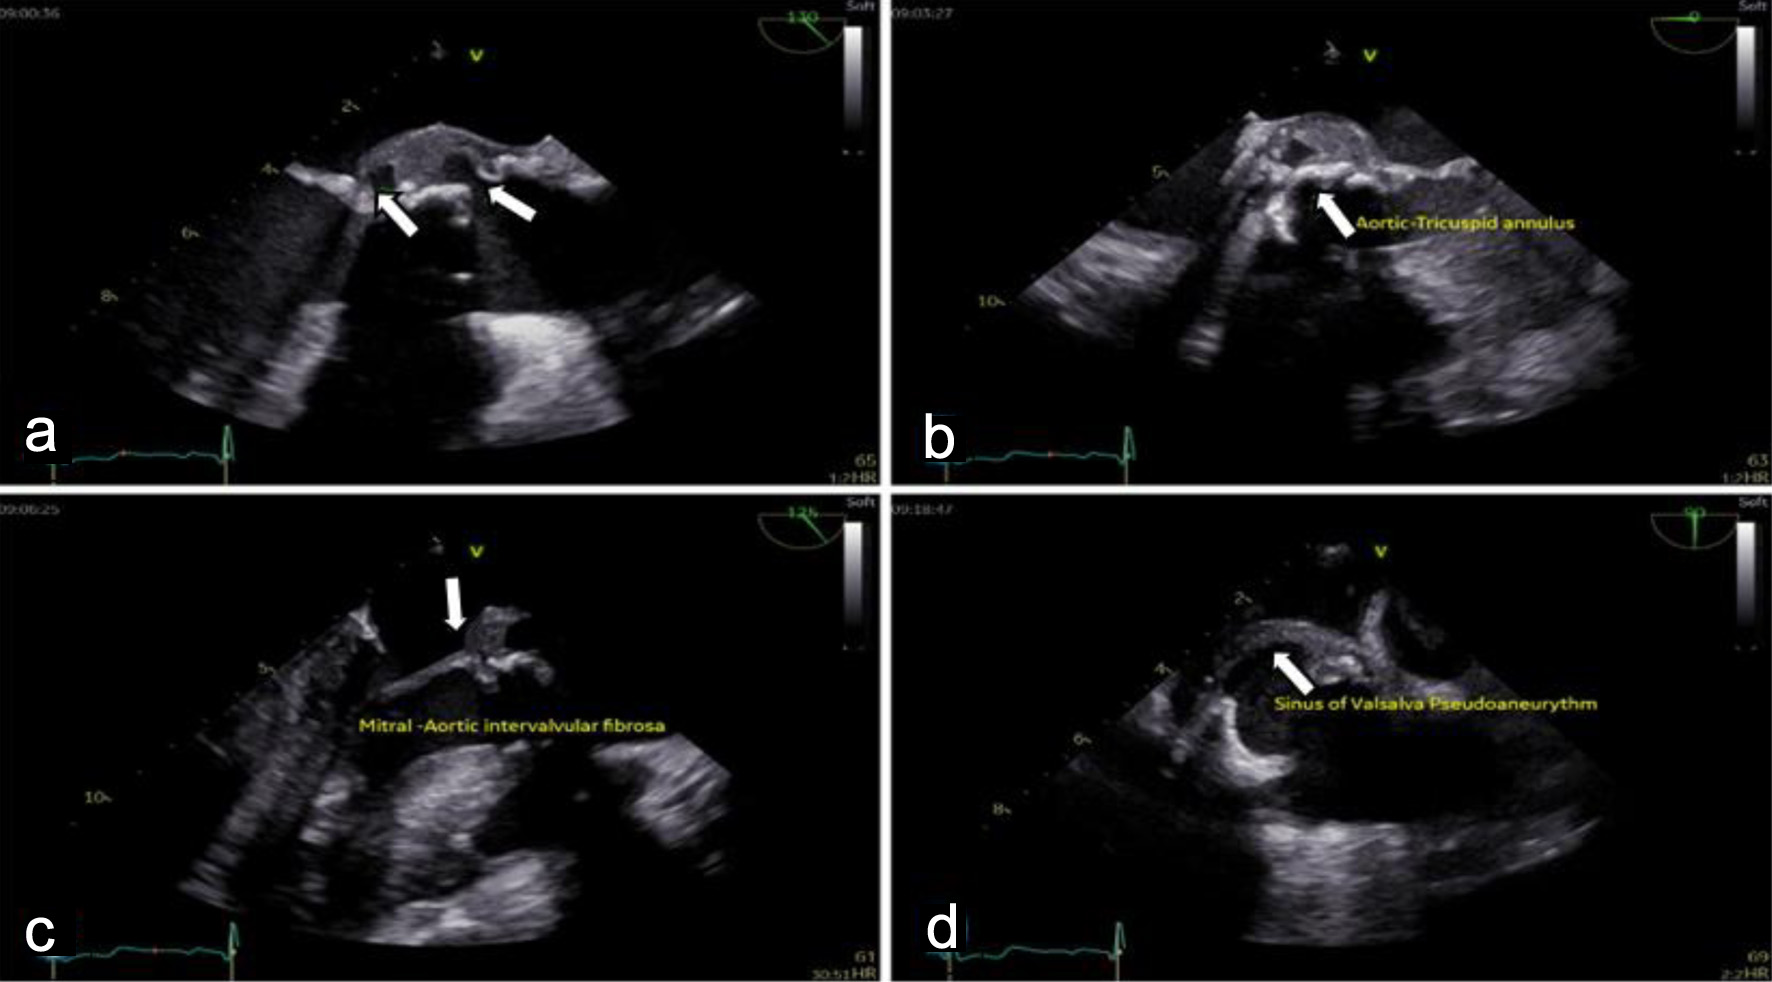

Cardiac evaluation was initiated with transthoracic echocardiography (TTE), which identified a mobile, pedunculated vegetation measuring approximately 3 × 6 mm attached to the prosthetic aortic valve suture line. The vegetation was associated with mild aortic regurgitation, while overall prosthetic valve function remained preserved. Left ventricular systolic function was maintained, with an estimated ejection fraction of 54%, and no signs of heart failure or significant ventricular dilation were observed. To further characterize the extent of valvular and periannular involvement, TEE was subsequently performed. TEE confirmed the presence of the prosthetic-valve vegetation and revealed a paravalvular aortic-root abscess (Fig. 2) extending into the sinuses of Valsalva and involving the mitral–aortic intervalvular fibrosa. These findings were indicative of advanced prosthetic-valve IE with periannular extension (Fig. 3), a condition traditionally associated with poor prognosis and strong indications for urgent surgical intervention.

Figure 3. Transesophageal echocardiography (TEE) shows destructive prosthetic aortic valve endocarditis with peri-annular extension: (a) large mobile vegetation attached to the bioprosthetic aortic valve cusps, (b) extension of infection to the aortic annulus with paravalvular aortic root abscess formation, (c) destruction of the mitral–aortic intervalvular fibrosa (MAIVF) (arrow), and (d) a sinus of Valsalva pseudoaneurysm (arrow).